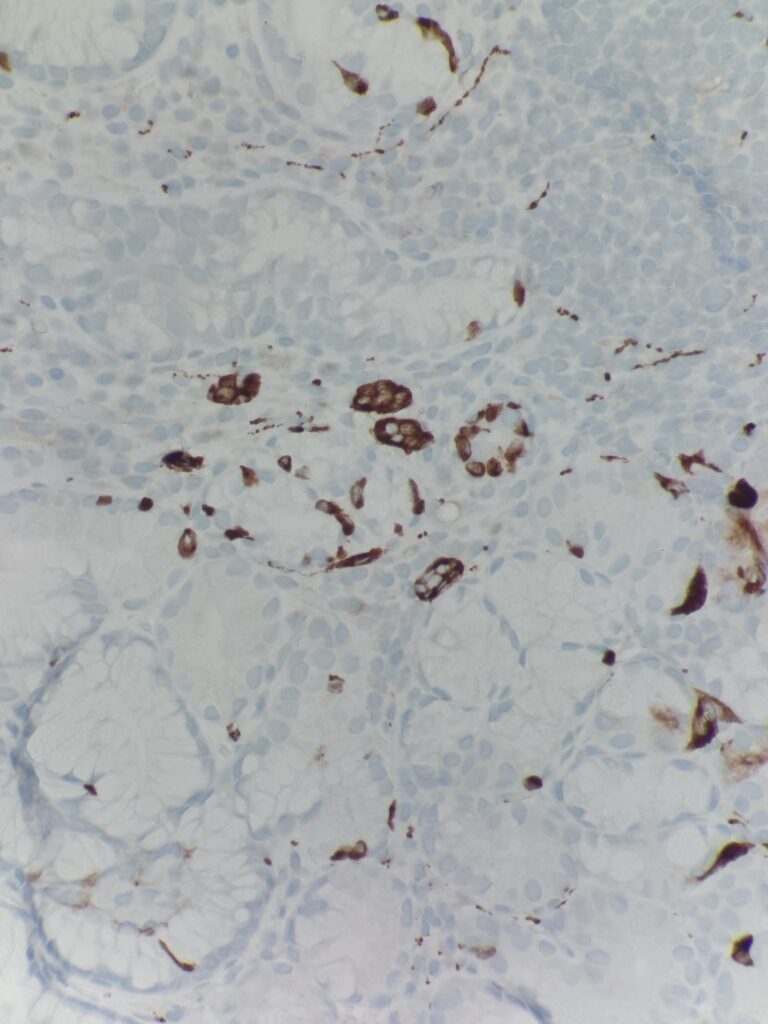

Diagnostic notes: As compared to H. pylori gastritis, the inflammation is predominantly in base of the mucosa extending to the superficial mucosa. There is loss of oxyntic glands, intestinal metaplasia, pancreatic acinar metaplasia and nodular and linear enterochromaffin like (ECL) cell hyperplasia. Gastrin stain can be used to differentiate antral vs. body mucosa – gastrin stain is positive in the antrum.